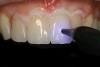

Fig 5. Preoperative photographs showing implant in place of maxillary left central incisor.

Figure 5

Fig 6. Preoperative photographs showing implant in place of maxillary left central incisor.

Figure 6

A 57-year-old woman presented to the dental office with a provisional fixed bridge replacing her maxillary central incisors. The abutment for the bridge was on her maxillary right central incisor, and the pontic was cantilevered off this abutment to replace a missing left central incisor (Figure 5 and Figure 6). The implant had been placed by a periodontist 6 months prior, and the patient was now ready to obtain her definitive implant-supported restoration. The need for the implant was due to a fractured endodontically treated tooth. The patient history revealed that she had been hit in the mouth with a stick as a teenager; her dentist at the time performed endodontic therapy on the left maxillary central incisor, followed by a metal post and core, and placement of a porcelain-fused-to-metal crown on both maxillary central incisors. Two years prior to her current visit, the patient developed pain and tenderness at the apex of the left central incisor, and a radiograph revealed a radiolucent apical lesion. A computed tomography (CT) scan was taken, and an endodontist determined that the tooth was not restorable due to a vertical root fracture. She was referred to a periodontist, who extracted the tooth, placing an osseous graft at the time of extraction for socket preservation, then replaced the extracted tooth with a cantilever pontic. Four months later, an implant was placed and the provisional was cemented back into place. A phone conversation with the periodontist who placed the implant revealed the type of implant used and confirmed that the implant was ready to be loaded and restored.